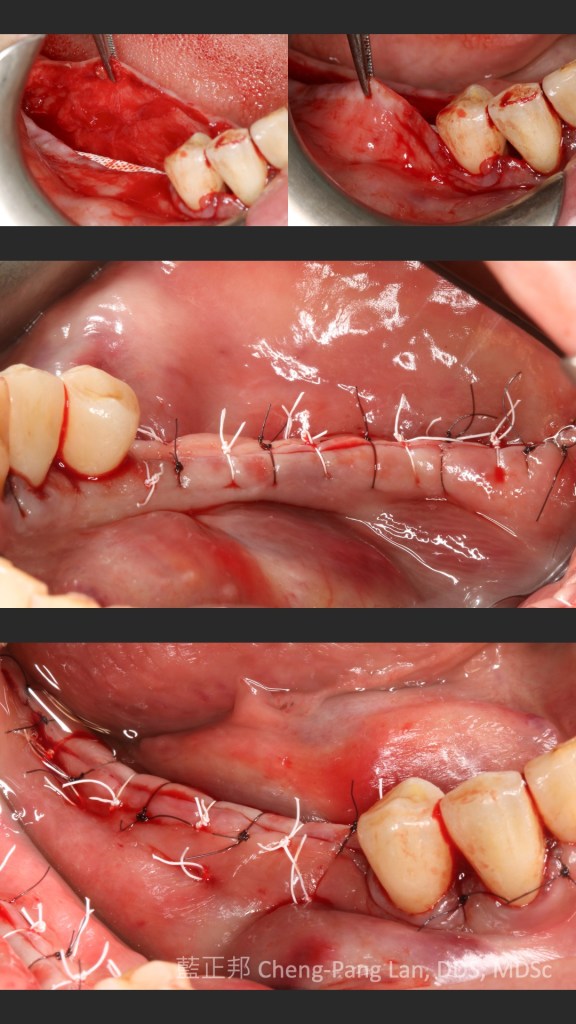

●第十一章垂直補骨,前一版的作者Massimo Simion,改成了Istvan Urban,果如我2016年判斷的,Istvan Urban已成為垂直補骨的接班人,連主編Buser也這麼認為(笑)。這邊寫的是簡易版,若朋友有興趣詳細的垂直補骨,直接看Urban寫的兩本垂直補骨書即可,我這邊也有第二本Vertical 2心得。但是十一章關於頰側與舌側的皮瓣鬆弛,寫得簡潔扼要,值得詳讀。

●第十四章補骨病發症,Isabella Rocchietta當年待過Massimo Simion的團隊內,有不少不可吸收再生膜併發症的處理經驗,這篇雖然文字多,但寫得很完整。Rocchietta的能力很強,把文獻整理非常好,從手術前就要考量的因素,到手術中,手術後都有。同時也有新的不吸收再生膜暴露的處理分類,自己看了蠻有收穫,同時,從最後的引用文獻,再回推思考為何Rocchietta引用?很有意思。